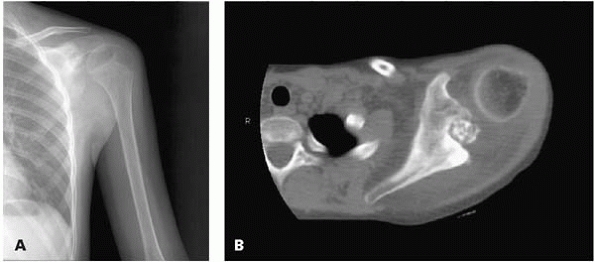

![]() |

|

▪ FIGURE 17-3 This boy presented with shoulder pain. (A)

This AP radiograph of the shoulder was read as normal by the radiologist, who did not have the benefit of the history and physical exam. Fortunately, the orthopaedist reviewed the radiograph closely and recommended a CT scan. (B) This CT cut shows a large lesion in the scapula, which was later identified as an osteoblastoma. |